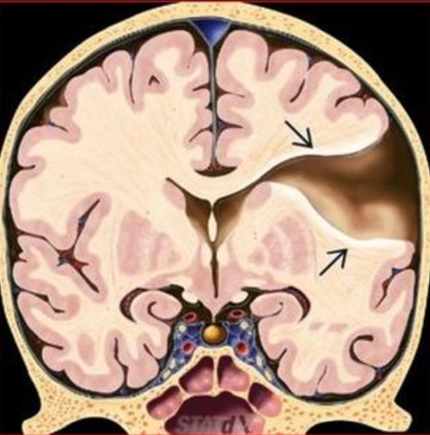

Não trước không phân chia thể không phân chia (Alobar holoprosencephaly)